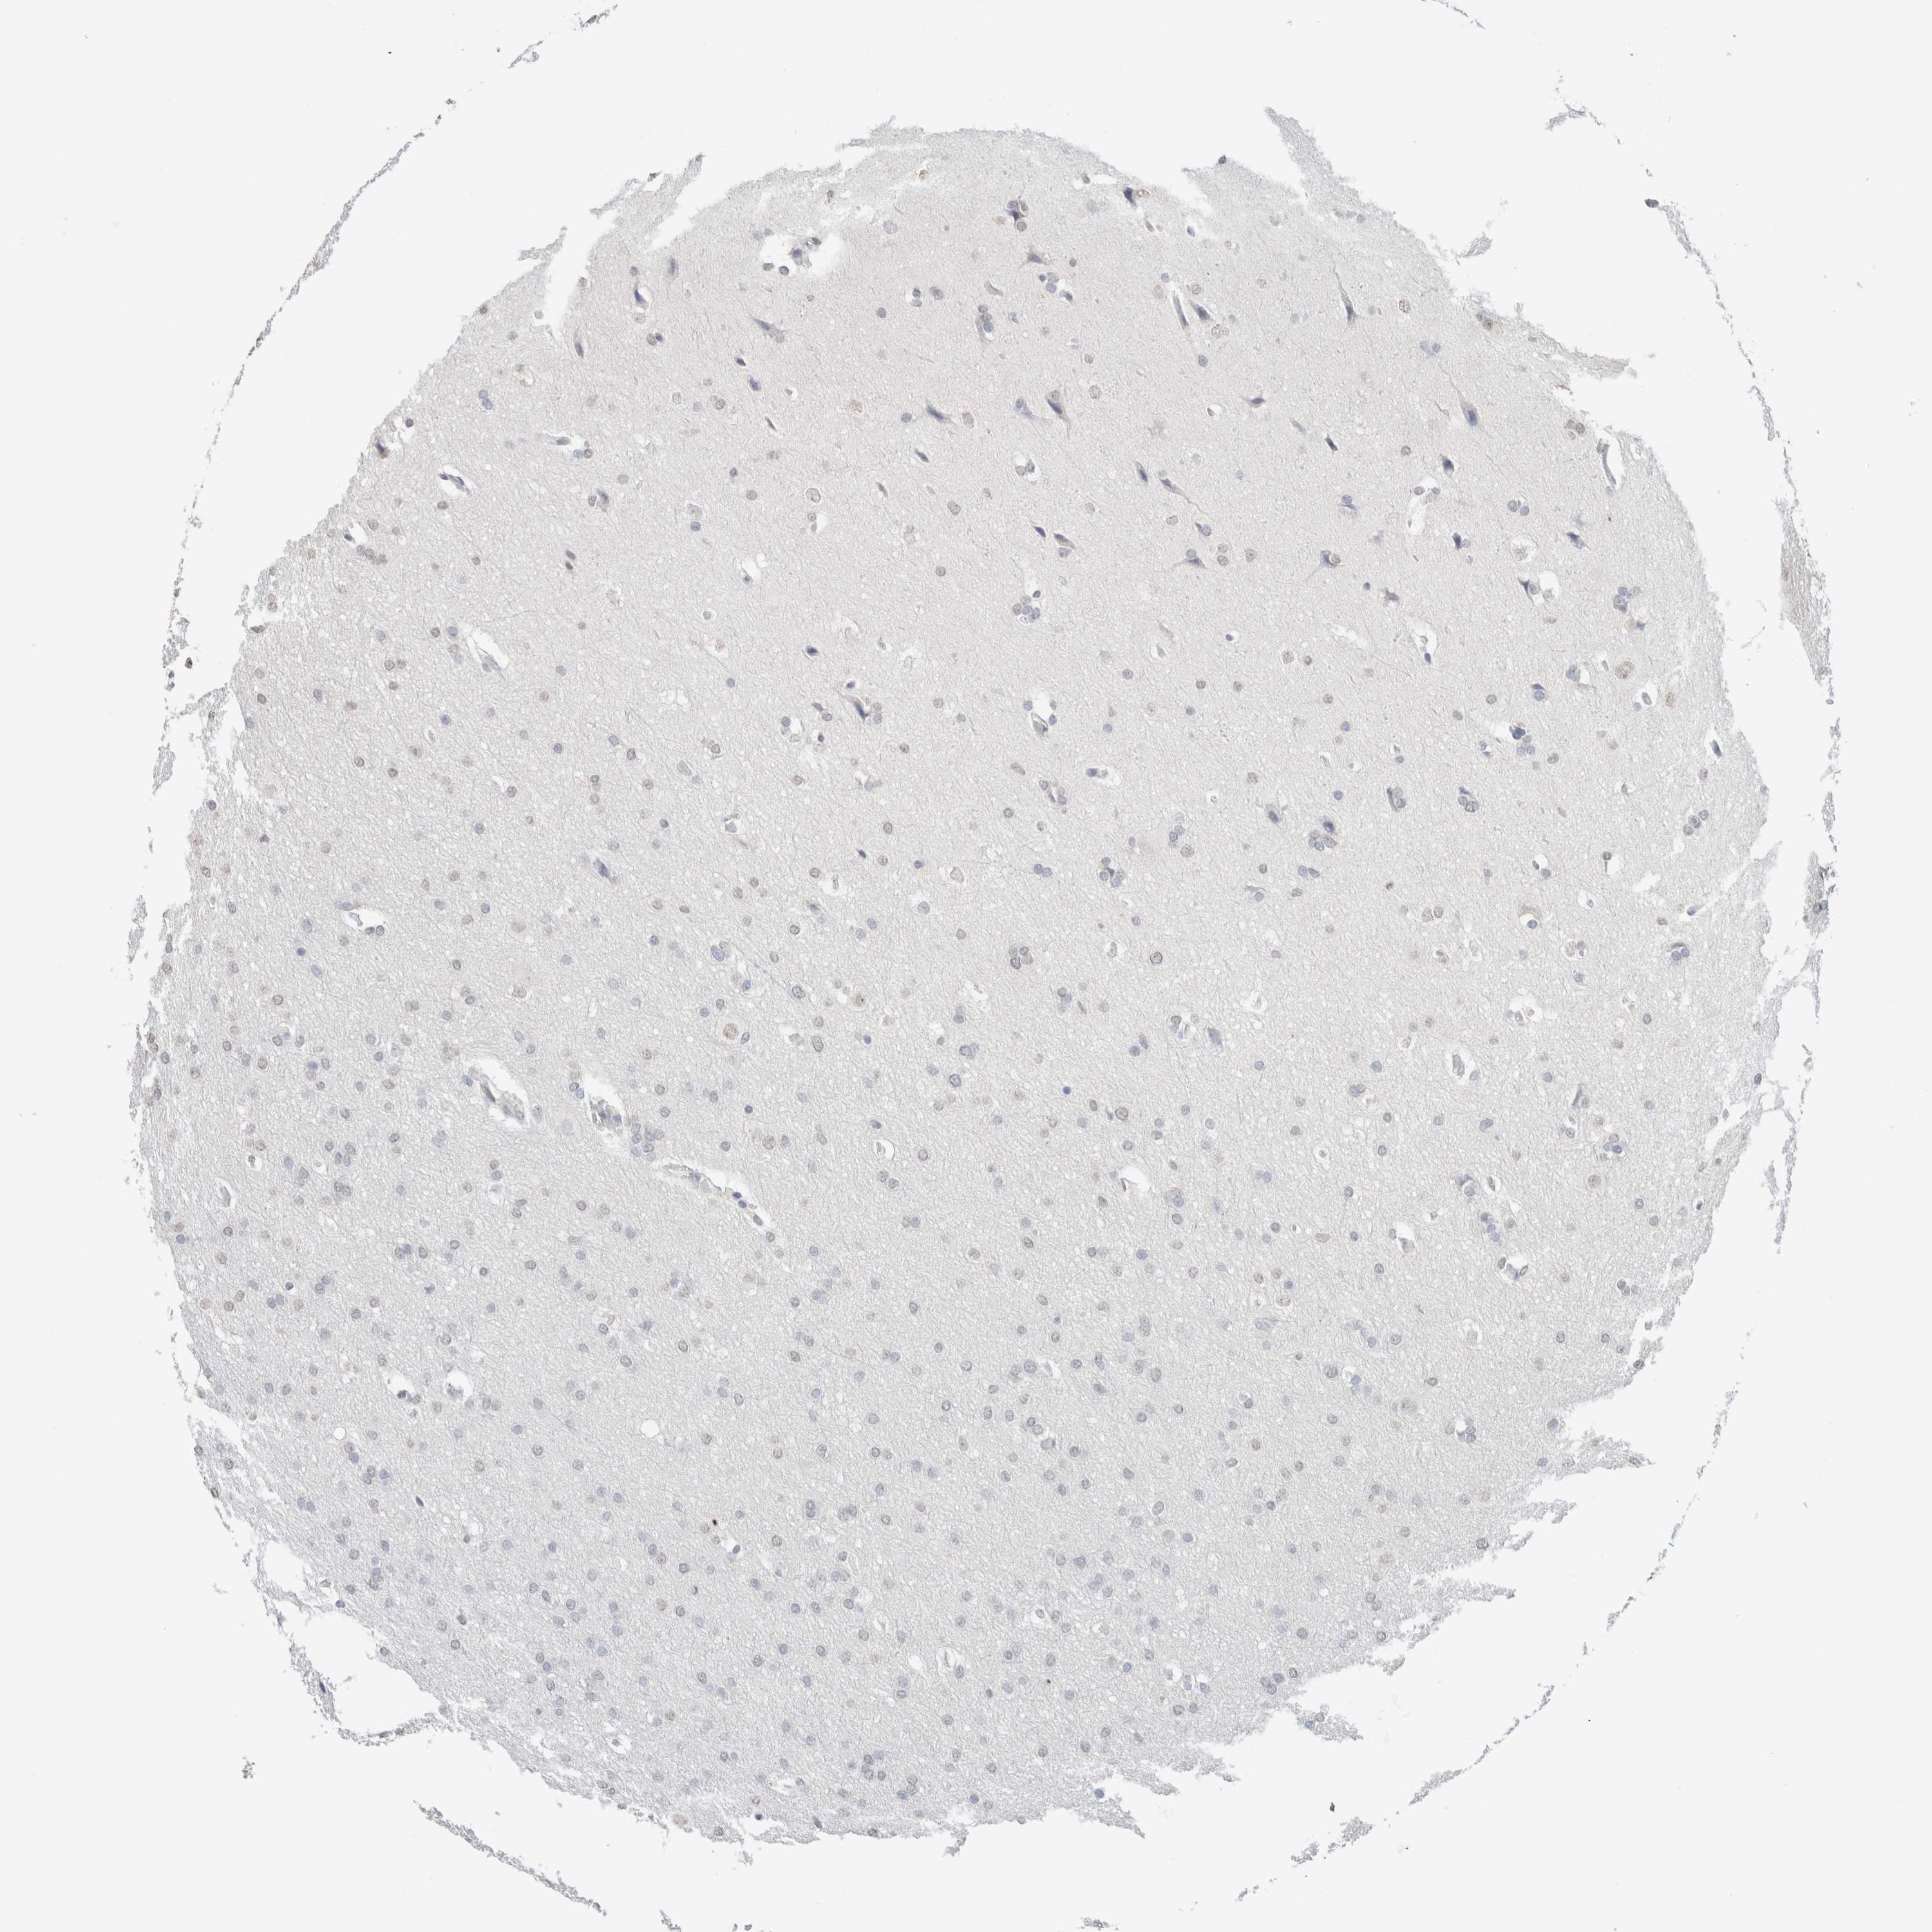

GLIOMA - Protein expressioni

A mouse-over function shows sample information and annotation data. Click on an image to view it in a full screen mode. Samples can be filtered based on level of antibody staining by selecting one or several of the following categories: high, medium, low and not detected. The assay and annotation is described here.

Note that samples used for immunohistochemistry by the Human Protein Atlas do not correspond to samples in the TCGA dataset.

Antibody stainingi

Antibody staining in the annotated cell types in the current human tissue is reported as not detected, low, medium, or high, based on conventional immunohistochemistry profiling in selected tissues. This score is based on the combination of the staining intensity and fraction of stained cells.

Each image is clickable and will lead to virtual microscopy that enables deeper exploration of all samples and also displays staining intensity scores, fraction scores and subcellular localization as well as patient and tissue information for each sample.

Antibody HPA050092

Antibody CAB025368

Glioma, malignant, High grade

Glioma, malignant, Low grade